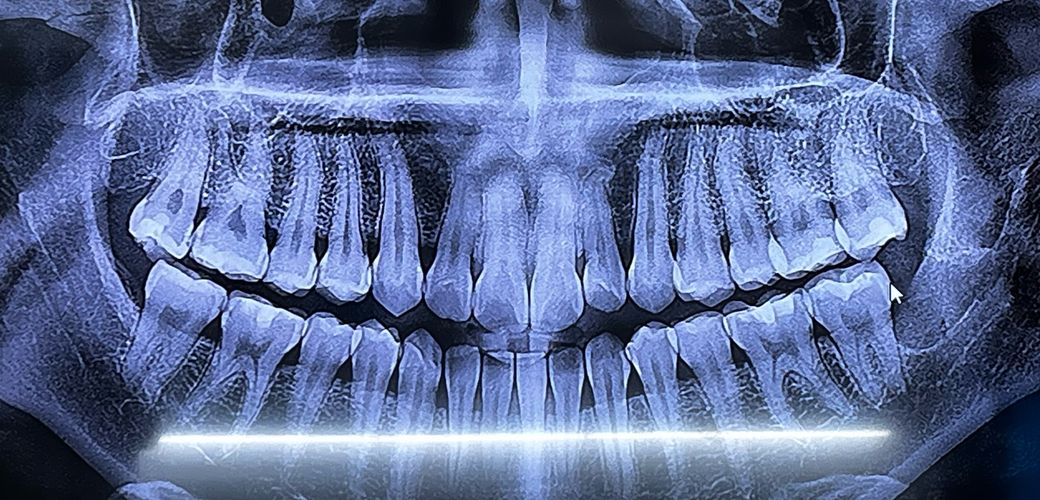

파노라마로만으로 봤을때는 신경치료에대해 필요한지 아닌지 볼 순 없겠지만 그래도 전문가분들이 보시기엔 어떨지 궁금합니다..

오른쪽 아래 2개의 어금니 인접면에 충치가 있는 것으로 보입니다. 충치의 크기는 크지 않은 걸로 보여 충치를 제거하고 나서도 신경치료를 할 가능성은 높지 않습니다.

인접면이 포함된 충치의 경우에는 치아의 모양을 잘 만들어주기 위해 레진보다는 인레이 치료를 하는 경우가 많습니다.